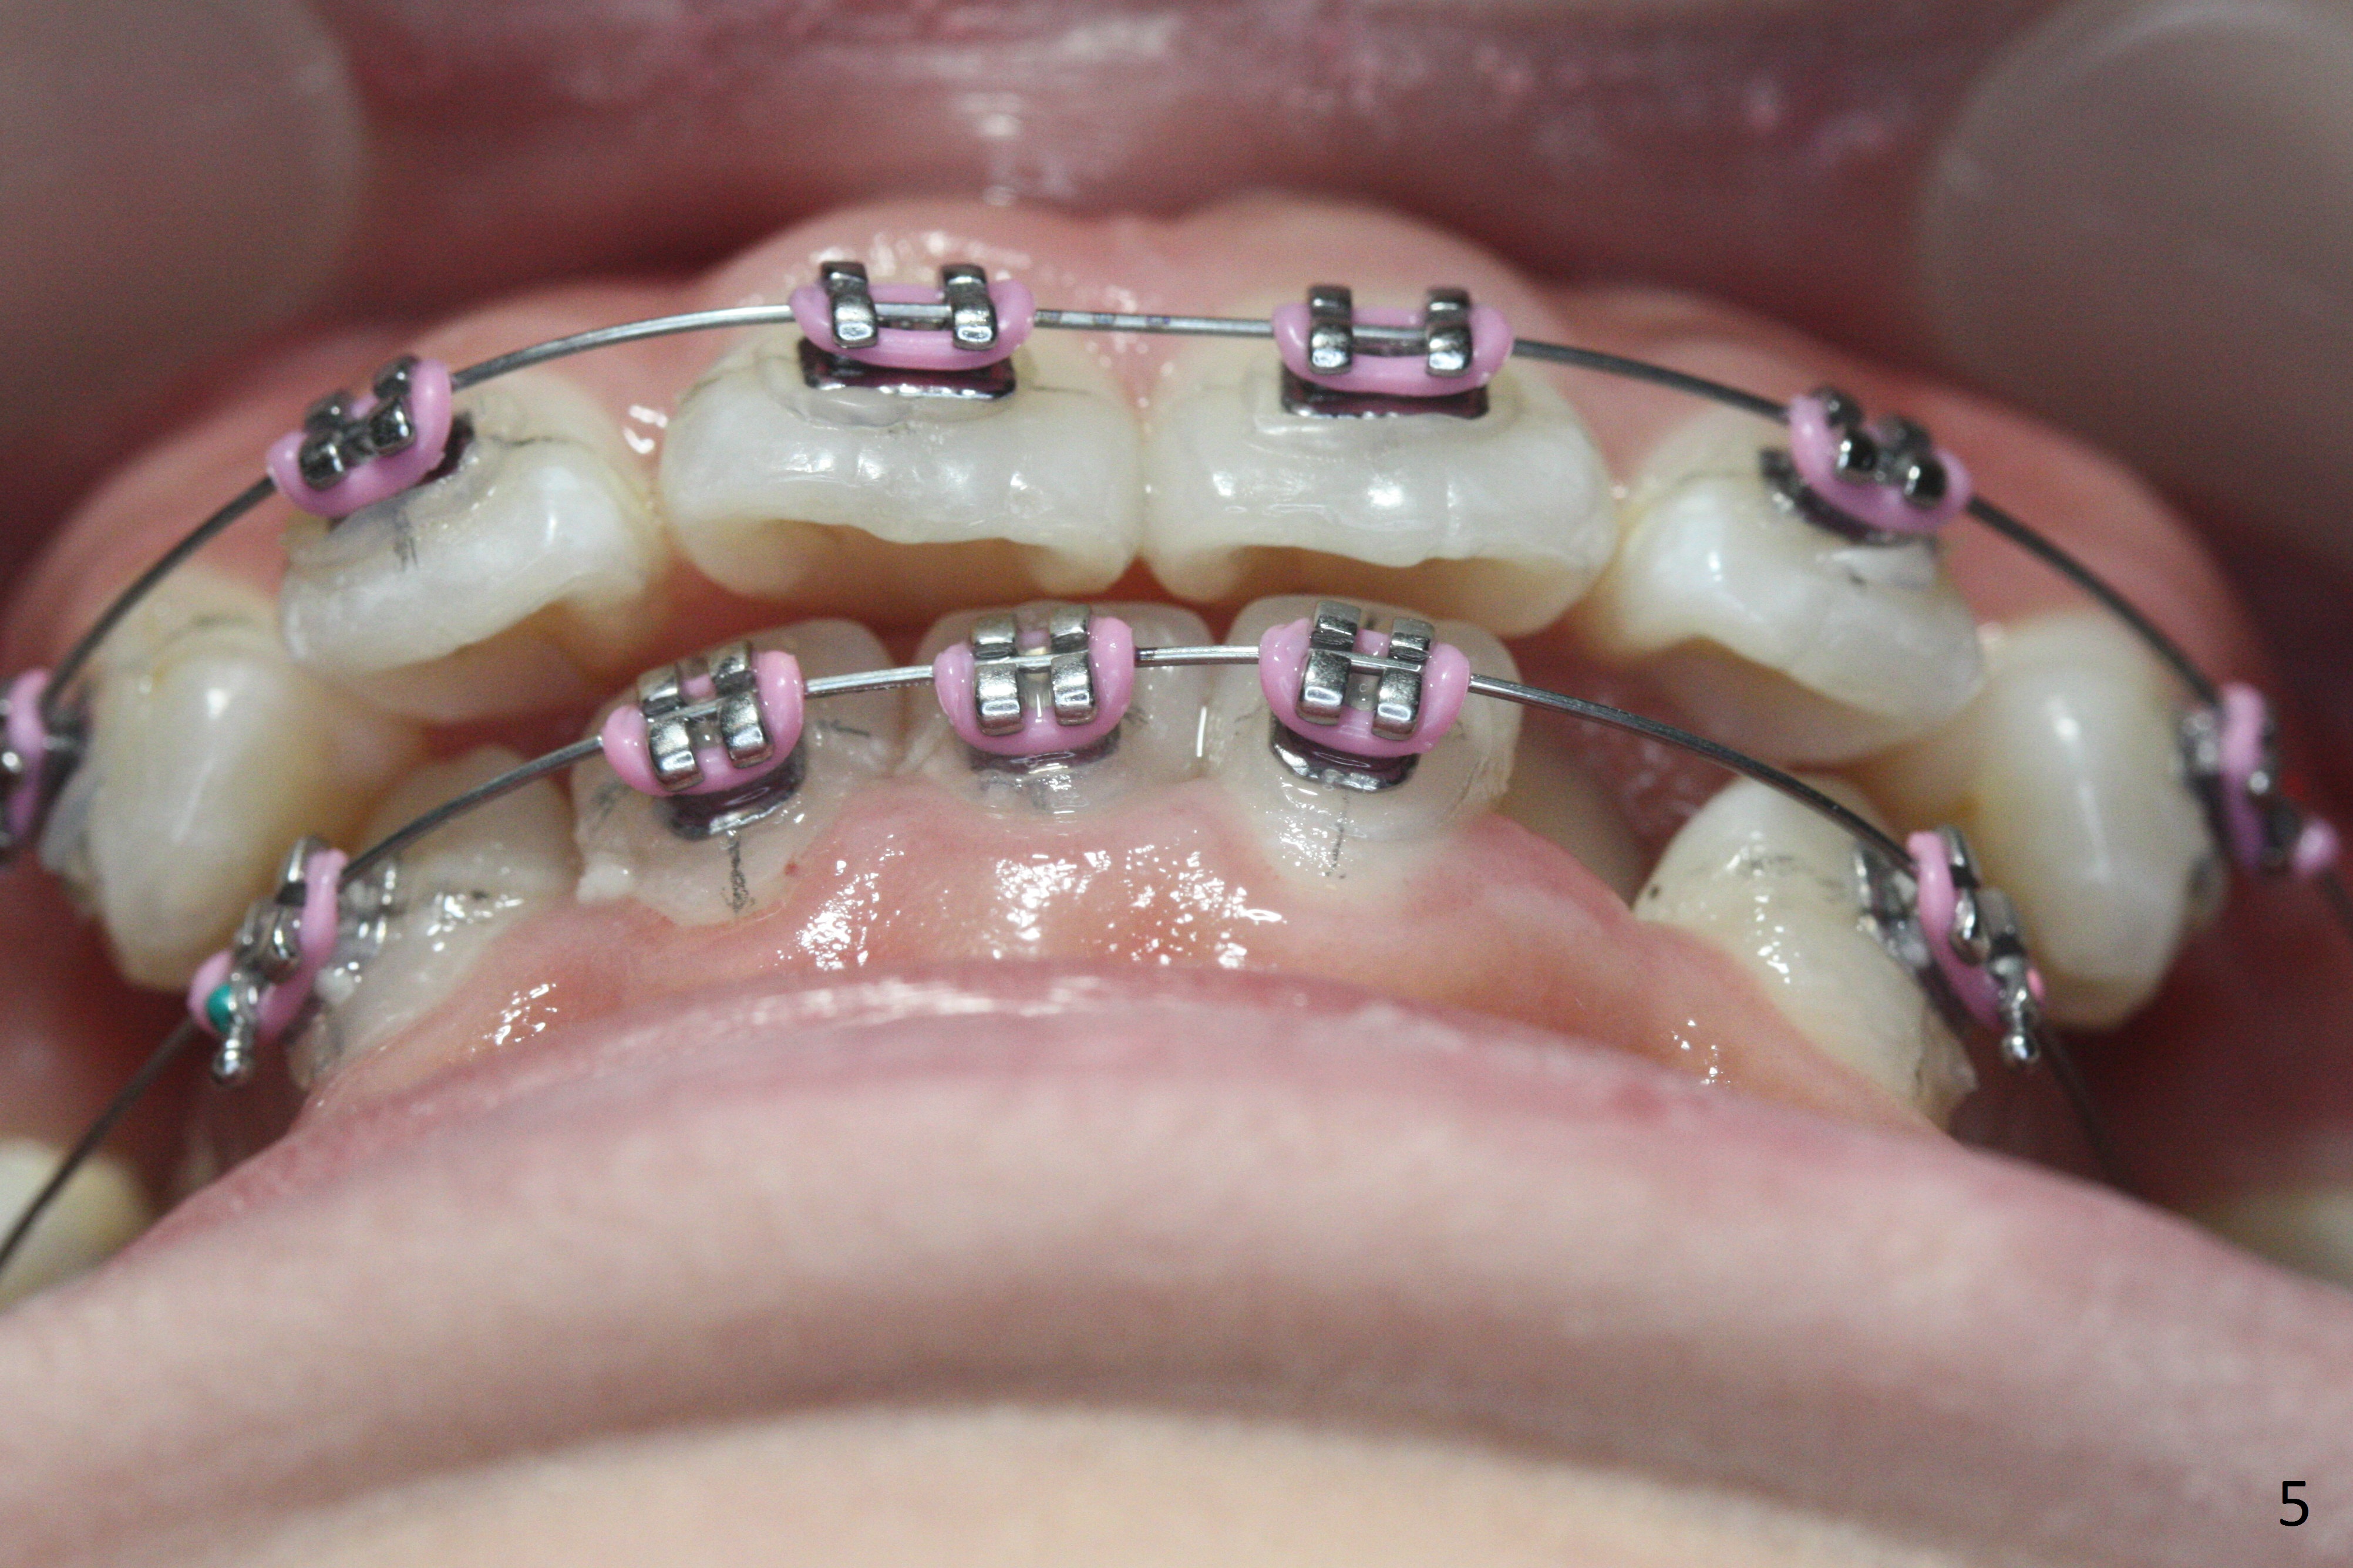

In fact there is enough space for banding at LL6 with reuse of 12 niti (Fig.4). Anterior crowding improves 1 month post banding (Fig.5, as compared to Fig.1-3); there is no difficulty in place 14 niti wire between UL 5 and 6 (Fig.6, as compared to Fig.3), since UL5 has been lingualzied.